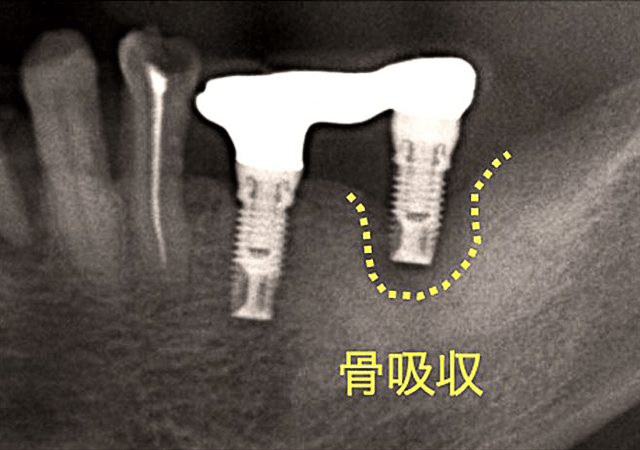

インプラント周囲疾患とは、インプラントの周囲組織に炎症が起こる疾患で、歯周病と同じ細菌感染症の一種で、歯面ではなくインプラントの表面に付着した細菌性プラーク・バイオフィルム(歯垢)が原因で起こります。インプラントは深部では骨が周囲に存在し、浅い部分では歯肉粘膜に接して存在します。インプラントの周囲が適切に清掃されていないと、インプラントの表面と骨の部分で、インプラントの歯周病が生じはじめます。これらの細菌が炎症を起こすことで、やがて歯槽骨が破壊されてインプラント周囲の骨吸収を起こします。このインプラント周囲疾患は、インプラント周囲粘膜炎とインプラント周囲炎の2つの異なる炎症性病変に分けることができます。初期のインプラント周囲組織の炎症性病変は、インプラント周囲粘膜炎と呼ばれ、インプラント周囲粘膜からの出血と腫れを特徴とし、骨の吸収は伴いません。治療も比較的容易に治癒が望めます。これは、歯では歯肉炎にあたります。インプラント周囲粘膜炎が、さらに進行すると、インプラント周囲炎へと炎症性病変は重症化し、さらに病状は進みます。これは、インプラント周囲の骨の吸収を伴い、治療は困難を伴います。歯では、歯周病(歯周炎)にあたるものです。(Berglundh T et al. 2018)

インプラント周囲骨の吸収(ぐらつき)

インプラント周囲の骨の破壊(骨の吸収)が進むことによって、インプラントが周囲の骨に固定されない状態になります。放っておくと徐々にひどくなり、抜け落ちてしまうこともあります。